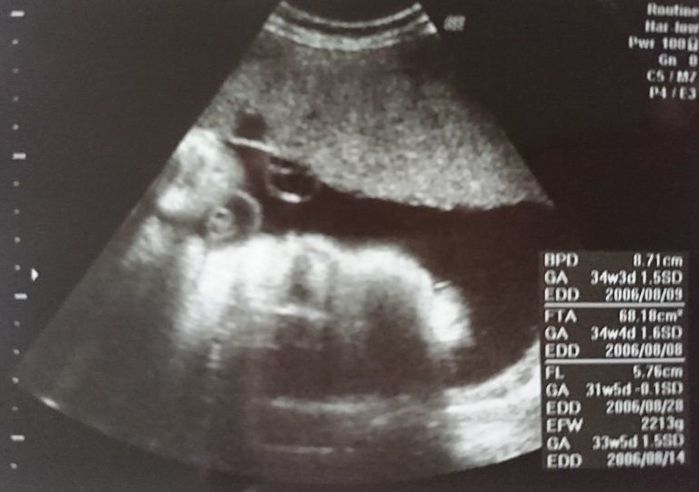

妊娠33週目のエコー写真

おなかが大きくなり、胃を圧迫してあまり食べられなくなってきました。大きなおなかでの通勤はかなり厳しく、産休に入るのを指折り数えていた日々でした。電車で席を譲ってもらえたり、会社で周囲の人が気遣ってくれたのがとても嬉しく、人の温かさに救われていた時期でした。夜中におなかの中で動き回るので、寝不足になっていた時期です。赤ちゃんの推定体重は2213gでした。